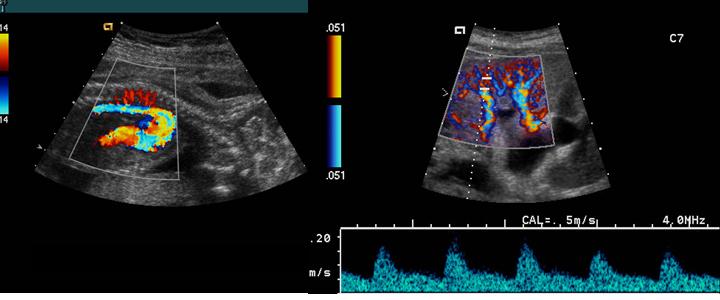

Mosaic

A mottled appearance caused by turbulent flow

Jet

A localized area of higher flow through and after an area high grade stenosis

Subclavian steal

abnormal flow direction into the subclavian from the vertebral artery caused by stenosis of the subclavian

- Subclavian artery has a severe stenosis or occlusion

- Vertebral artery must compensate for the reduction of flow

- Becomes a collateral pathway to the extremity

- RETROGRADE flow or abnormal flow present in the vertebral arter